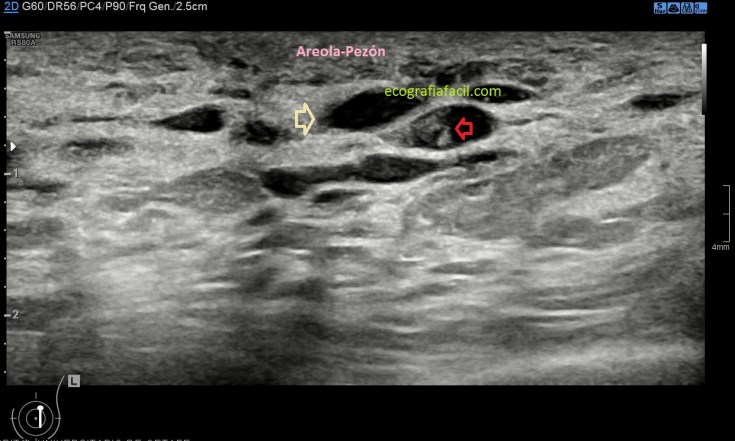

En la imagen 2 observa como ves los conductos, estos son numerosos y anecoicos, llamativa y marcadamente negros todo ellos sin excepción. Ectasia ductal, que si es en ambas mamas, será bilateral, que es lo normal.

En la imagen 3 puedes ver conductos dilatados y donde puedes ver algunos anecoicos y otros ecogénicos, estos últimos marcados con flechas rojas igual que en la imagen 4. Ojo siempre a estos hallazgos.

En la imagen 4 observas un conducto con contenido ecogénico que ocupa gran parte de ese conducto, a tramos, sin evidencia de contenido ecogénico nodular. Es muy importante aportar el dato de que el contenido ecogénico es móvil o no, puede ayudar a la radióloga.